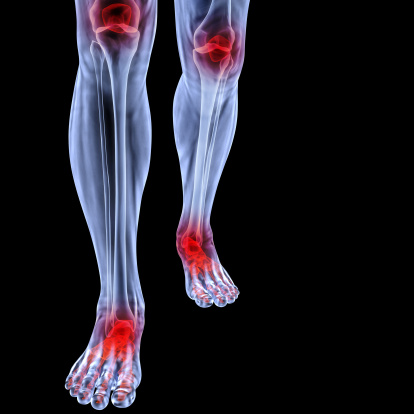

Improve Joint Health: Causes, Diet, & Lifestyle Changes

Joint inflammation can be caused by several things, but to improve joint health, it is imperative to know some foods that cause inflammation and also anti-inflammatory foods. Inflammation in joints can present itself in a variety of ways. For some people, it creates muscle soreness, pain, a burning sensation, or even an itchy feeling. It ...click here to read more